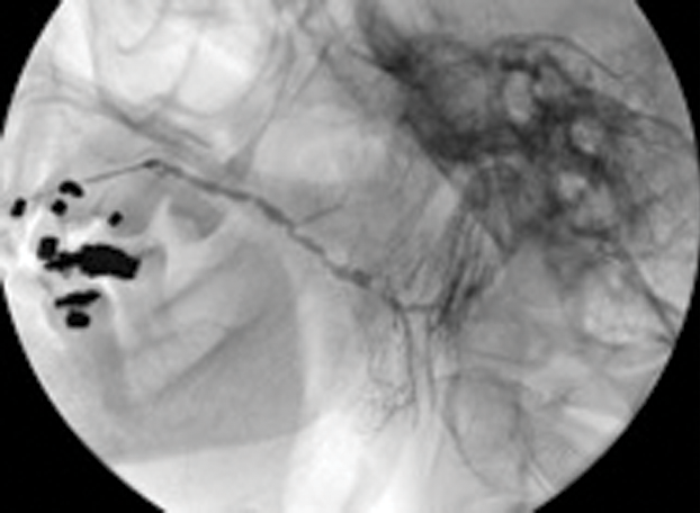

Figure 3: (A) The preoperative sialogram identifying a stone in the middle third of the submandibular duct.

Figure 3: (B) The insertion of a Dormia basket (closed).

Figure 3: (C) The stone trapped in the open basket.

Treatment of salivary calculi by interventional sialography

Miniature Dormia baskets can be inserted into the major salivary ducts under x-ray or ultrasound guidance and manipulated to pass and grasp small stones. The procedure is performed under local anaesthesia (by direct infiltration of the buccal oral mucosa or inferior dental nerve block). The trapped stone is then withdrawn to the duct ostium, where a small relieving papillotomy incision may be needed to release the stone. It is important to maintain regular salivary flow through a papillotomy site, if this has been necessary to release a stone during extraction in a Dormia basket, in order to prevent healing over of the duct orifice. This may be done by prescribing regular hydration and use of sialogogues, assisted by gland massage.

Case selection is best performed on the basis of preoperative sialography. Ideally the stone should be within the main extraglandular duct, mobile and no more than 20-25% wider than the distal duct running from stone to ostium [12].

Duct strictures lying between the stone and duct orifice may require dilatation by balloon ductoplasty but should always be viewed with caution as they are invariably densely fibrotic and may still impede stone removal.

Success in clearance of stones using Dormia baskets is reported to range from 60-100%. This technique therefore offers a simple, effective, highly non-invasive cure which is achievable in one visit with minimal morbidity. In avoiding general anaesthesia it offers treatment options to patients with other more serious co-morbidities.